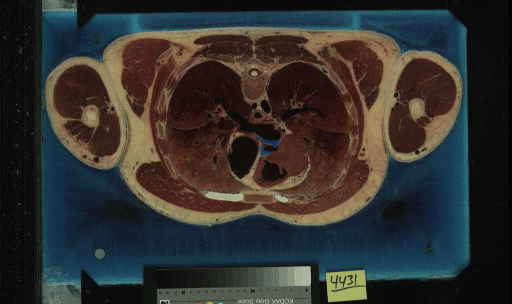

The skin and muscle models were extracted from the cryosection slice data from the Visible Human Project

male dataset. Below, an example slice from the dataset is pictured. The cryosection data was chosen for

a number of reasons. First of all, muscle does not show up well (or at all) on CT scans. Muscle tissue

is easily segmented from the rest of image by simply searching for red. Secondly, the skin was distorted

in the CT scans in the area of the nose. When they "zoomed in" to get higher resoltution images of the

brain, the area of the nose was outside the scanner's field of view. As you can see in the second image,

the nose remains perfectly intact in the cryosection data.

Slice from Midsection of Body